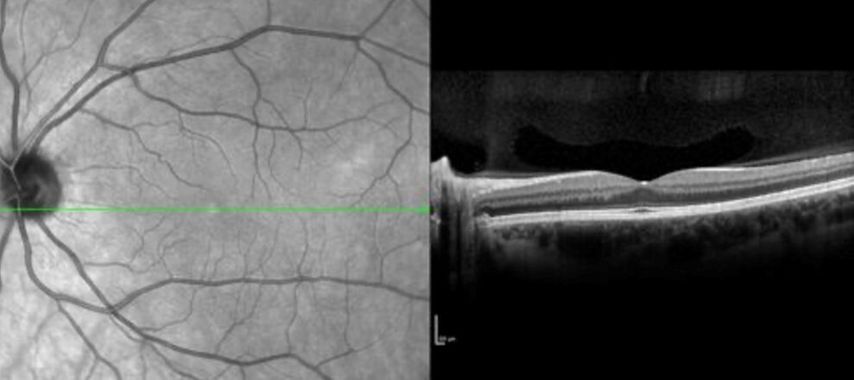

Die Messung von retinaler Schichtatrophie mittels der optischen Kohärenztomographie (OCT) ermöglicht eine zuverlässige Bestimmung neuroaxonaler Schädigung für das Monitoring des Krankheitsverlaufs bei Multipler Sklerose (MS). Eine neue Studie gibt Einblick in die Rolle der Genetik: Träger:innen des rs10191329-Risikogenotyps im DYSF–ZNF638-Locus zeigen in einer prospektiven RMS-Kohorte eine signifikant beschleunigte Atrophie retinaler Schichten in der OCT. Pro Risikoallel nahm die jährliche Atrophierate der peripapillären retinalen Nervenfaserschicht (pRNFL) um 0,10% pro Jahr und der Ganglienzell- und inneren Plexiformschicht (GCIPL) um 0,11% pro Jahr zu – unabhängig von Alter, Krankheitsaktivität, Therapie und Ancestry-Komponenten. Die Befunde stützen die Hypothese einer genetisch vermittelten neuroaxonalen Vulnerabilität jenseits primär immunologischer Mechanismen.

Abb. 1: Retinale OCT-Aufnahme einer MS-Patientin mit diskreter retinaler Atrophie (Bild: Gabriel Bsteh)